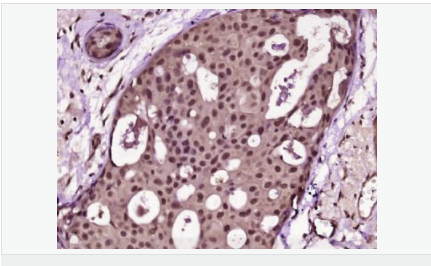

| 產品應用 | ELISA=1:5000-10000 IHC-P=1:100-500 IHC-F=1:100-500 Flow-Cyt=1μg/Test (石蠟切片需做抗原修復) not yet tested in other applications. optimal dilutions/concentrations should be determined by the end user. |

| 產品介紹 | Proliferation Marker Ki67 antigen is the prototypic cell cycle related nuclear protein, expressed by proliferating cells in all phases of the active cell cycle (G1, S, G2 and M phase). It is absent in resting (G0) cells. Ki67 antibodies are useful in establishing the cell growing fraction in neoplasms (immunohistochemically quantified by determining the number of Ki67 positive cells among the total number of resting cells = Ki67 index). In neoplastic tissues the prognostic value is comparable to the tritiated thymidine labelling index. The correlation between low Ki67 index and histologically low grade tumours is strong. Ki67 is routinely used as a neuronal marker of cell cycling and proliferation. Function: Thought to be required for maintaining cell proliferation. Subcellular Location: Nucleus. Chromosome. Predominantly localized in the G1 phase in the perinucleolar region, in the later phases it is also detected throughout the nuclear interior, being predominantly localized in the nuclear matrix. In mitosis, it is present on all chromosomes. Similarity: Contains 1 FHA domain. SWISS: P46013 Gene ID: 4288 Database links: Entrez Gene: 4288 Human Entrez Gene: 17345 Mouse Omim: 176741 Human SwissProt: P46013 Human SwissProt: Q91VE6 Mouse Unigene: 689823 Human Unigene: 80976 Human Unigene: 4078 Mouse Unigene: 233802 Rat Important Note: This product as supplied is intended for research use only, not for use in human, therapeutic or diagnostic applications. 細胞增殖標志物(Proliferation Marker) Ki67與PCNA一樣,為細胞增殖的一種標記,在細胞凋亡中S、G2 、M期均有表達,G0期缺如。 Ki-67增殖指數(shù)高低與許多腫瘤的分化程度、浸潤、轉移以及預后密切相關,因此被廣泛作為各種惡性腫瘤的必檢項目之一。 |